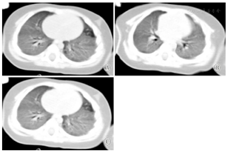

X线胸片提示双肺弥散渗出性病变,见图1。胸部螺旋CT平扫+增强提示双肺对称性斑片状毛玻璃样模糊影,见图2。

注:A:1 d;B:4 d;C:10 d;D:17 d

入院后予低流量吸氧,经皮氧饱和度(SpaO2)维持在93%~96%,先后经验性使用哌拉西林-他唑巴坦、口服阿奇霉素、头孢吡肟+万古霉素抗感染,静脉滴注氨溴索及布地奈德、可必特雾化等治疗。入院第4天纤维支气管镜检查提示呼吸道黏膜炎症。X线胸片示双肺弥散渗出性病变加重,见图1。入院第10天气促、呼吸困难加重,出现明显呼吸窘迫症状,SpaO2波动在87%~90%,咳嗽时伴口唇发绀,肺部听诊细湿啰音增多,复查床边胸片提示双肺弥散渗出进行性加重,见图1。改用气管插管机械通气,初始参数设置:吸入氧体积分数(FiO2)80%,呼吸道峰压(PIP)2.5 kPa,呼气末正压通气(PEEP)0.6 kPa,压力支持1.5 kPa, SpaO2维持在90%~95%。入院第10天在CT引导下经皮肺穿刺活检术,手术顺利。病理诊断:(肺)间质性炎症病变,见图3。应用甲泼尼龙2 mg/(kg·d)静脉滴注,1次/d,用药3 d后呼吸困难明显缓解,逐渐下调呼吸机FiO2、PIP、PEEP,复查胸片提示肺部渗出逐渐吸收好转,见图3。然后拔除气管插管改为鼻罩呼吸机辅助呼吸,3 d后脱离呼吸机改为鼻导管低流量吸氧,撤机后激素改为甲泼尼龙1 mg/(kg·d),静脉滴注,1次/d,3 d后改为泼尼松1 mg/(kg·d)口服,2次/d,7 d后停吸氧,激素总疗程14 d,住院25 d出院。出院时偶有干咳,无呼吸困难,一般情况好,出院后未继续口服激素。出院3个月门诊随访,患儿病情稳定,偶有咳嗽,无气促、呼吸困难,复查胸片示肺部阴影基本吸收;出院5个月电话随访一般情况好,无明显呼吸道症状,体质量增长良好。